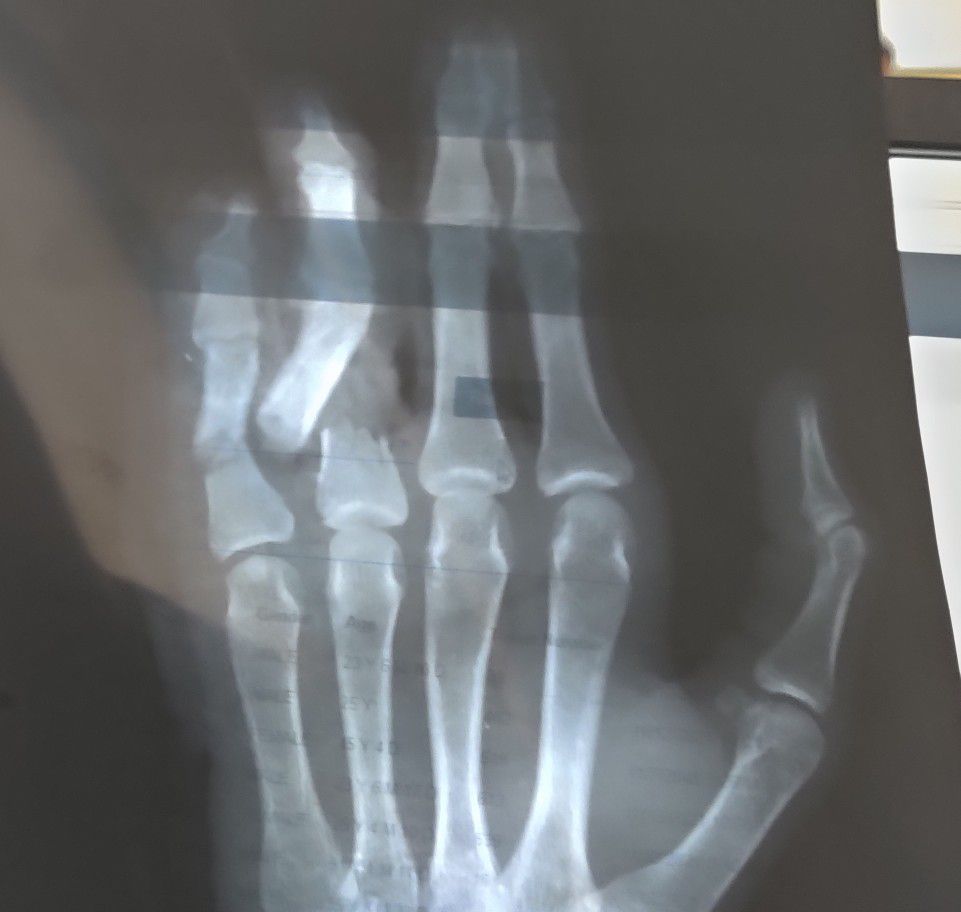

Fracture 4th and 5th Phalanx

Fractured

Phalanx